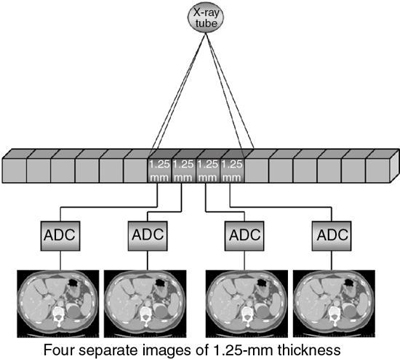

A CT detector consists of basically two major components: a radiation sensor coupled to suitable electronics, such as photodiodes, and analog-to-digital converters (ADCs; see Chapter 4). Although the radiation sensors convert x-ray photons to light, the photodiodes convert the light into electrical current (signal) that must be digitized before it is sent to a digital computer for processing. The electronics are carefully configured to the sensor elements (cells) of the CT detector and represent the data acquisition channels. As seen in Fig. 12.21, the detector consists of 16 elements or cells, each 1.25 mm in size, and the x-ray beam is collimated to fall on four of these cells. Therefore, four signals are collected per gantry rotation from each of the four cells and sent to the four ADCs to produce four slices, each 1.25 mm thick. For eight 1.25-mm thick slices, the x-ray beam would fall on eight detector elements. For four 2.5-mm thick slices, the beam would be collimated to fall on eight detector elements, where two 1.25-mm elements would be combined to produce a 2.5-mm thick slice, and so on. This electronic combination (or binning) of detector elements is described in more detail later in this chapter.